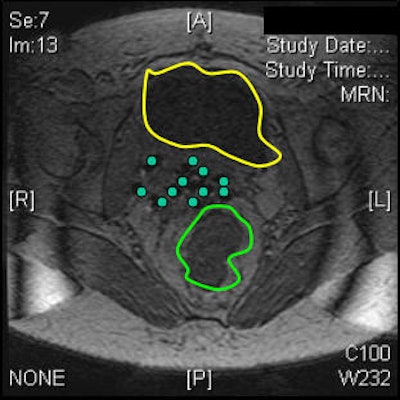

| Tumor volume on MRI (above) and CT (below). Images courtesy of Dr. Akila Viswanathan. |

Based on the DVH analysis -- done with CT volumes because that is the standard, Viswanathan added -- the median tumor volume was 80 cc. The median V150 was 60%, the median V90 was 82%, and the median V95 was 90%.

"For bladder and rectal DVHs, we saw that the median bladder total volume was 68 cc. We then calculated the 2-cc and 5-cc percent-of-treatment to the bladder volume and it was 80% and 70%, respectively," she said. "The median rectal volume was contoured for 55 cc and we saw that the 2-cc and 5-cc volumes were 90% and 80% of our prescription."

"We concluded that MR-guided interstitial brachytherapy is feasible. It does prevent the insertion into the bladder and rectum. It does allow conformal treatment planning and accurate delineation of the tumor, bladder, and rectum," she stated.